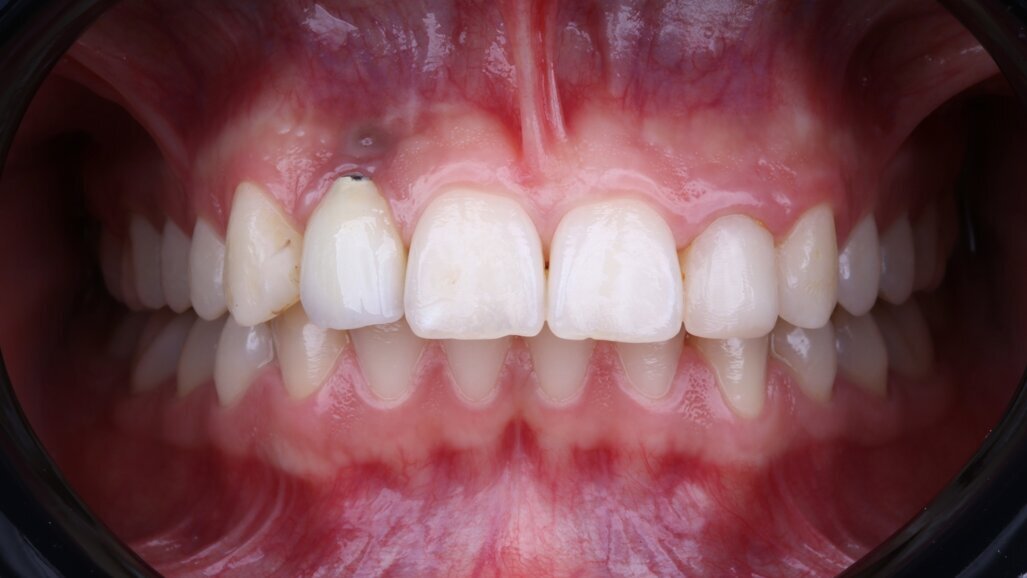

Fig. 9: Definitive prosthesis delivery: porcelain-veneered zirconia crown cemented on to a titanium link abutment.

After approximately three months, a final impression was captured, and a definitive porcelain-veneered zirconia crown was fabricated and cemented over a titanium hybrid abutment (Fig. 9). The occlusion was carefully adjusted, and the patient was enrolled in a structured maintenance programme with four-month recall intervals. At the one-year follow-up, the implant demonstrated excellent clinical and radiographic outcomes, showing stable soft tissue and no signs of inflammation or bone loss. The patient reported full satisfaction with the aesthetic and functional results.